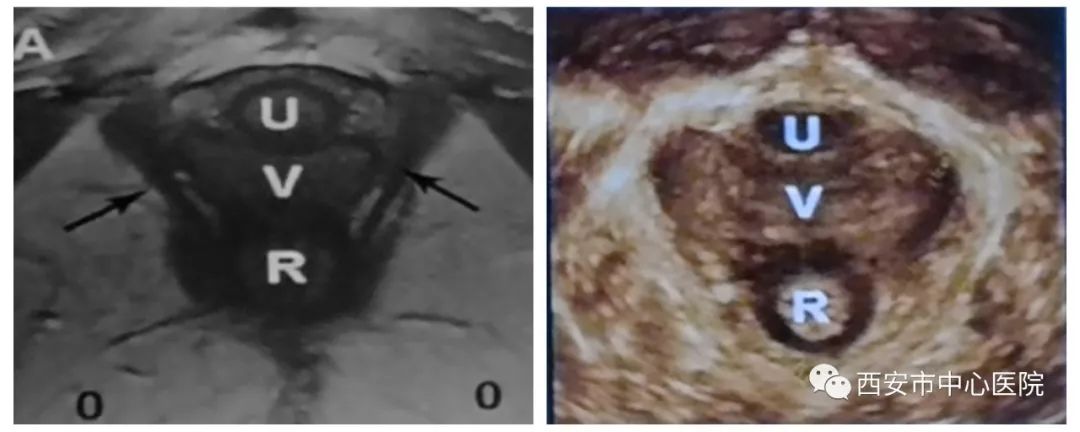

盆底超声包括二维超声检查盆底脏器有无脱垂及盆底四维成像检查盆底肌肉的完整性两部分。检查时将配备无菌保护罩探头放于会阴部,通过实时动态观察,比较患者静息、缩肛和Valsalva状态盆腔脏器结构和位置改变,直观反映子宫、直肠、膀胱等盆底器官的情况,可在临床症状出现之前做出早期诊断,为临床医生制定合理的治疗方案提供有力依据。

可以用来评估肛提肌裂孔的形态和变化(解剖层面);

可以发现及评估肛提肌及肛门括约肌损伤及程度;

2) 能够多平面成像(可获得轴平面,这对于肛提肌评估是必要的);TUI成像模式观察肛门括约肌;